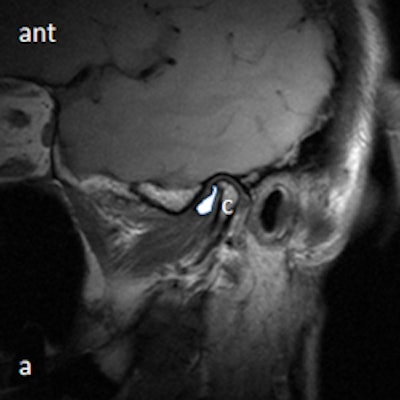

Dr. Friedman prefers that patients be supine on a stretcher with the jaw tilted away from the side to be examined. Then the person performing the ultrasound palpates the joint while the patient opens and closes her mouth. Gel is then placed on the joint, and the probe is placed at various positions around the joint. The images are examined to determine whether there is anterior displacement of the disk while the joint is the closed-mouth position.

"If the ultrasound is abnormal, the patient should be referred for an MRI, and any patient scheduled for surgery also must have an MRI," he said. "The main challenge is learning to detect what is normal on ultrasound. We also acknowledge that abnormal anteromedial and medially displaced disks may be missed or misinterpreted with ultrasound."